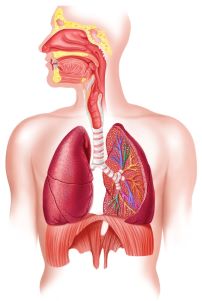

Herz und Darmgesundheit: Roemheld Syndrom

Das Roemheld Syndrom, oder auch Gastrokardiales-Syndrom bzw. Magen-Herz-Syndrom beschreibt eine Ansammlung von Symptomen, die durch übermäßige Gasansammlungen im Magen-Darm-Trakt ausgelöst werden. Die Ansammlung von Gasen führt zu einer Verschiebung des Zwerchfells in Richtung Brusthöhle. Gleichzeitig engt sich der Raum ein, den die Lungen und das Herz benötigen. Der Druck auf das Zwerchfell führt dazu, dass das Herz in seiner Höhle im Brustraum eingeengt wird. Dadurch kann es die volle Pumpleistung nicht entfalten.

Die Betroffenen verspüren Beschwerden des Herzens, insbesondere Brustenge, Herzstolpern und Brustschmerzen. Es kommt auch zu Sodbrennen-artigen Schmerzen, die hauptsächlich hinter dem Brustbein auftreten, aber auch zu Hitzewallungen, Kurzatmigkeit, Schwindelattacken und Atemnot. Durch eine Aktivierung des autonomen Nervensystems und auch des Schmerzempfindens in der Herzgegend werden häufig akute Angstzustände ausgelöst.